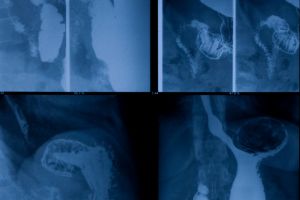

5

Identify abnormalities in the abdomen or other organs.